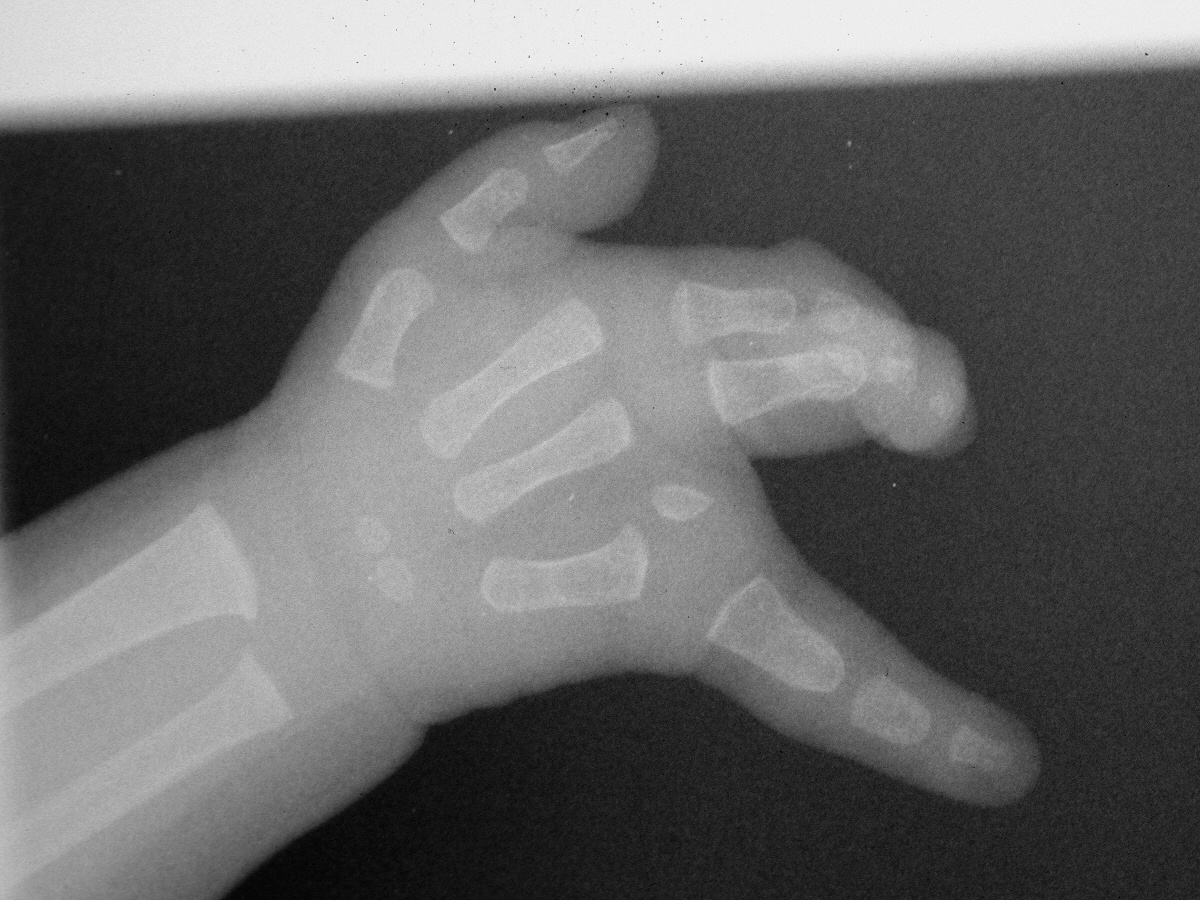

Further growth allowed better evaluation of the ulnar skeletal components.

The second procedure included web deepening with a three-flap plasty and closing wedge osteotomy to realign the small finger  metacarpophalangeal joint.

Postoperative result.